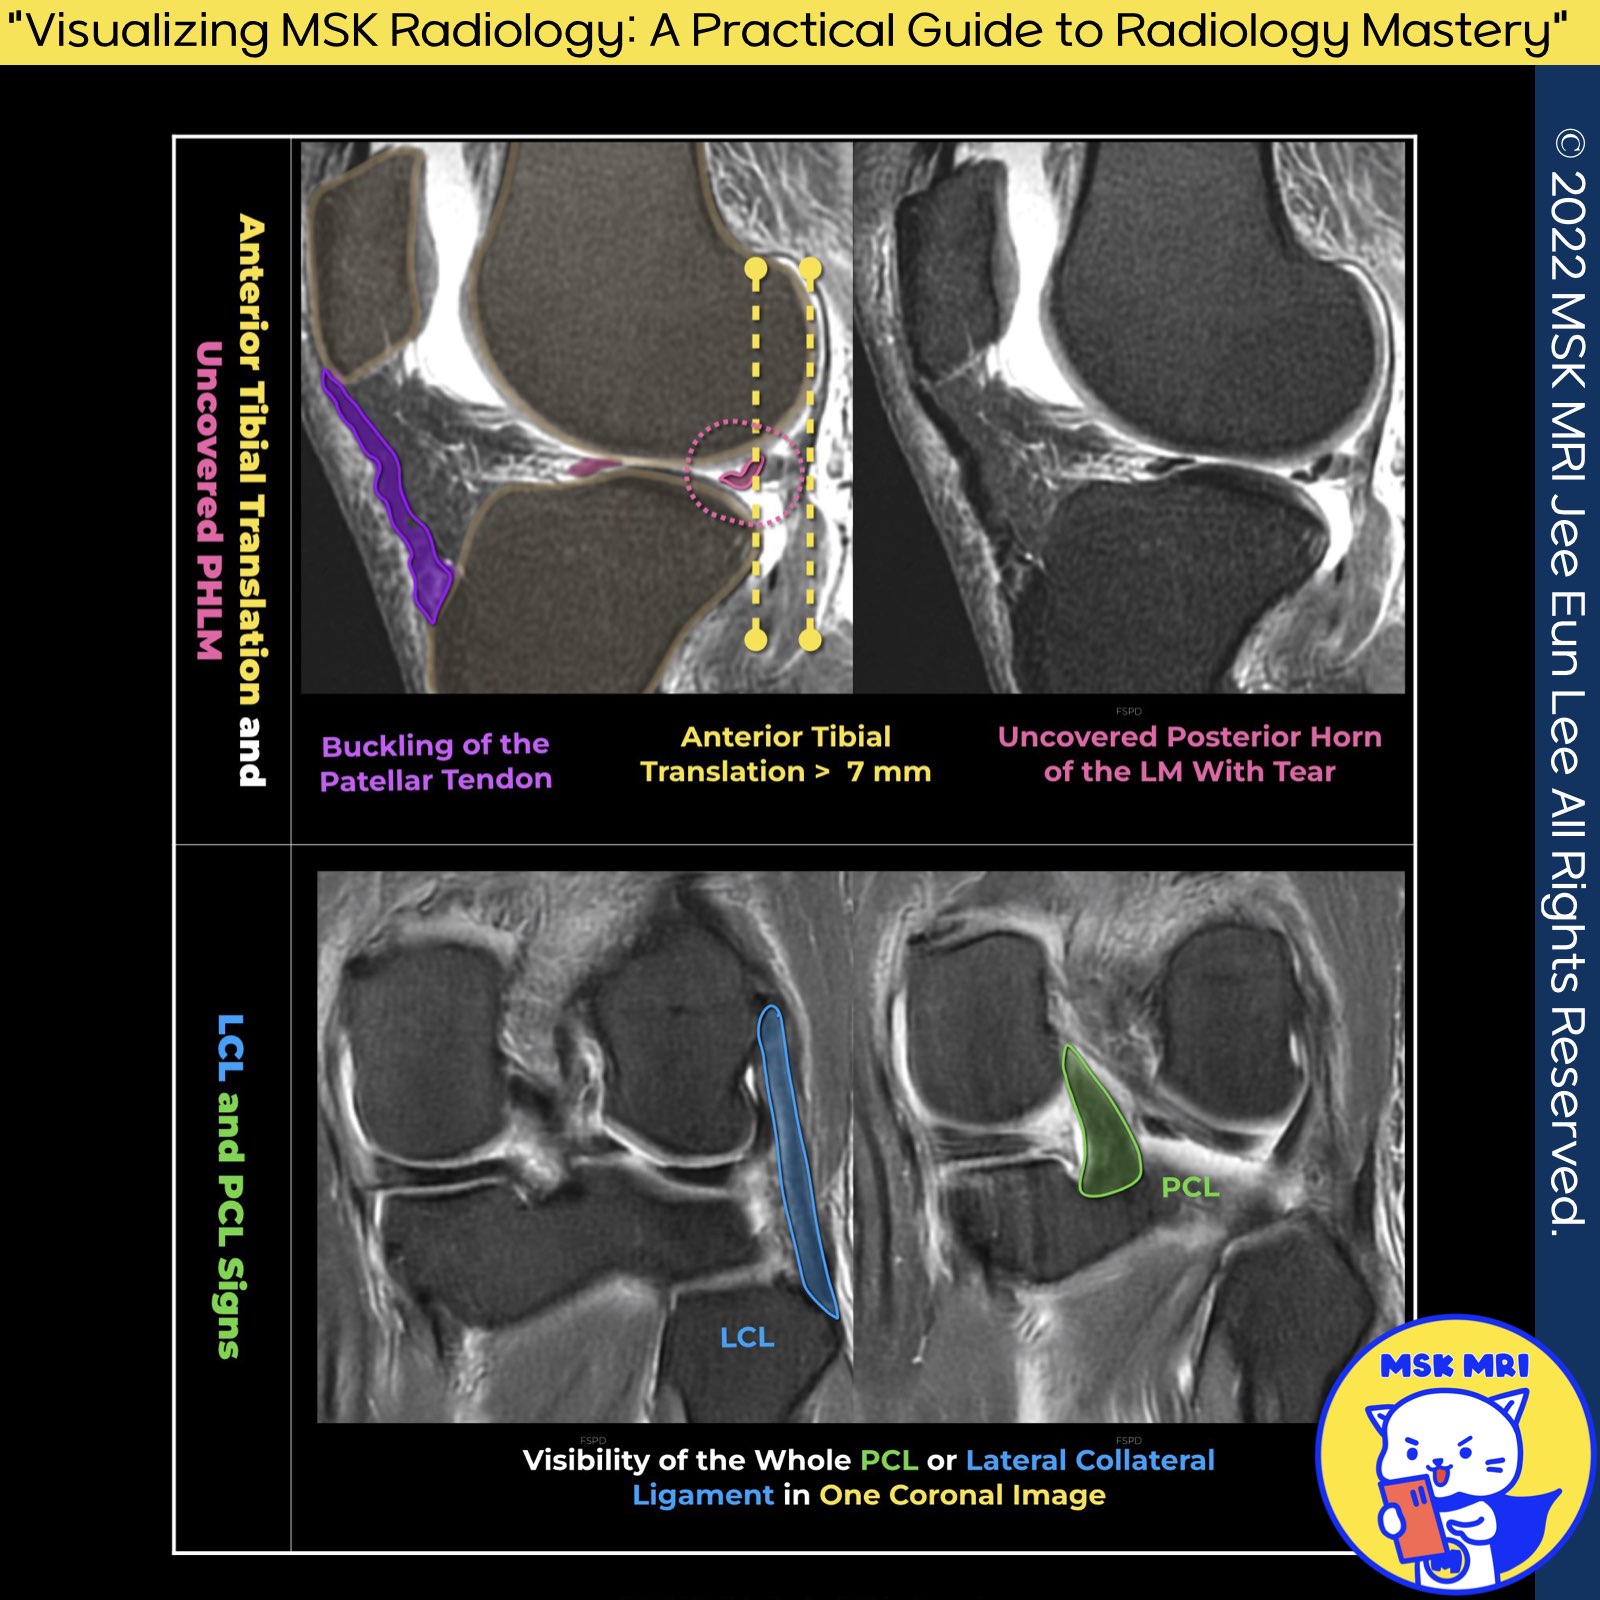

✅ Secondary Signs of ACL Injury

Secondary signs are highly specific indicators of an Anterior Cruciate Ligament (ACL) injury, though they are less sensitive compared to primary signs.

1️⃣ Anterior Translation of the Tibia (Anterior Tibial Translocation):

- The ACL prevents anterior movement of the tibia. In cases of ACL tears, increased anterior tibial translation, known as "anterior tibial translocation," is observed during knee extension.

- In complete ACL ruptures, this sign involves measuring anterior tibial translation relative to the lateral femoral condyle in the mid-sagittal plane.

- Translation between 5 and 7 mm is suggestive, while more than 7 mm confirms an ACL tear. This assessment also reveals potential lateral meniscus (LM) tears.

2️⃣ Uncovering of the Posterior Horn of the Lateral Meniscus:

- This sign indicates a posterior displacement of the lateral meniscus's posterior horn relative to the lateral tibial plateau's posterior aspect, hinting at an ACL injury.

3️⃣ Coronal Whole PCL and LCL Sign:

- The visibility of the popliteus tendon, Lateral Collateral Ligament (LCL), and biceps femoris on a single coronal image suggests an ACL tear.

- An acute ACL disruption causes anterior tibial translation, altering the LCL's orientation to a more coronal position.